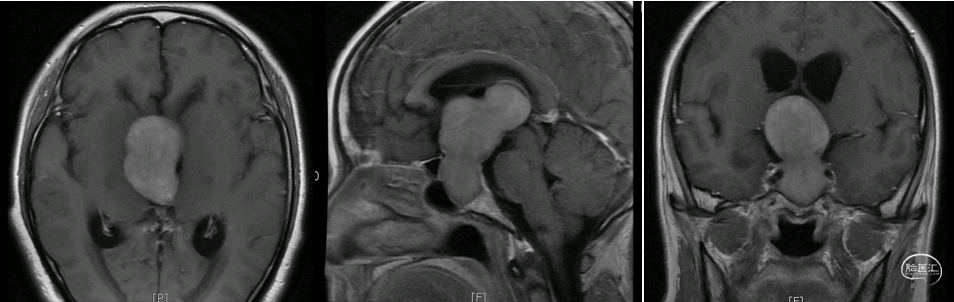

术前核磁示:巨大垂体腺瘤。

初步诊断:巨大垂体腺瘤。

依据术前影像学病灶位置拟定神经内镜下扩大经蝶入路切除肿瘤